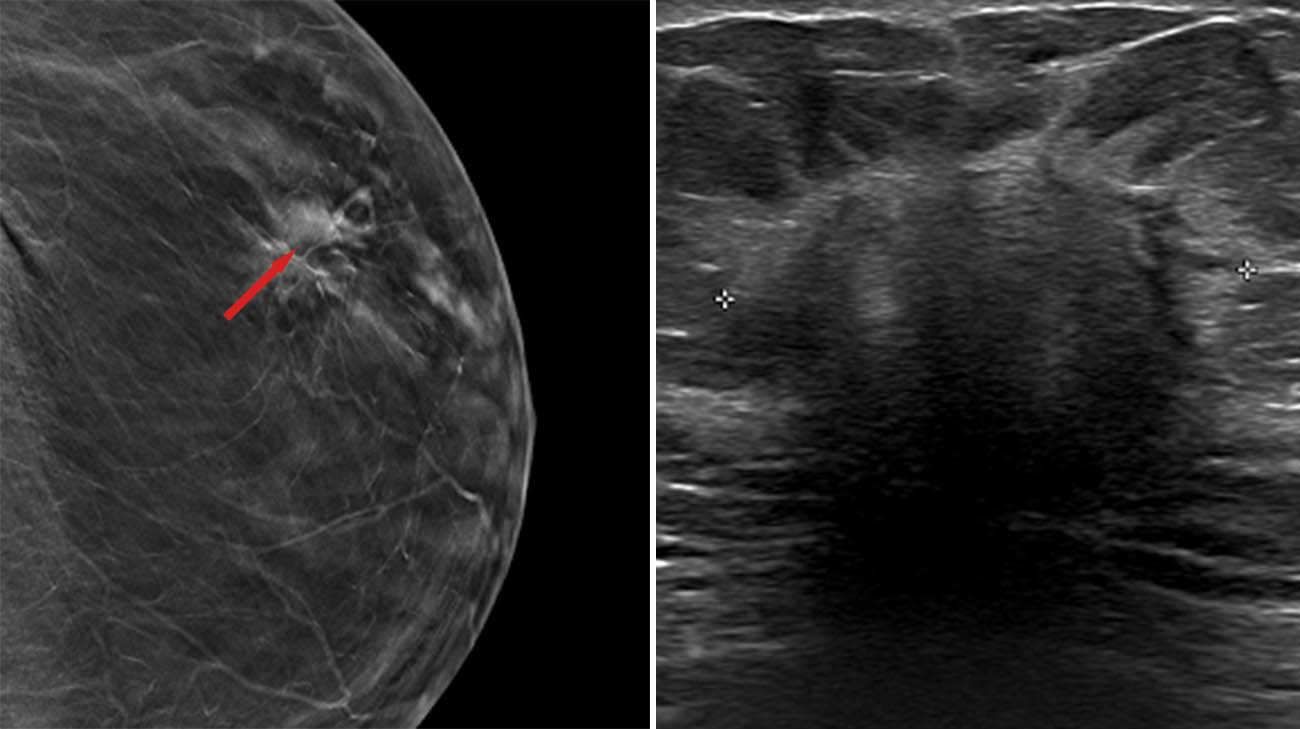

“The X-rays showed a worrisome mass on the left breast, about three centimeters large,” says Dr. Fenton, executive medical director of the McDowell Cancer Center and the Breast Health Center. “That’s bigger than we would like to find but still treatable. I was also worried about an enlarged lymph node under her left arm,” which could indicate the cancer had spread.

Following biopsies of both the tumor and the lymph node, the picture became clearer. Virgie had invasive lobular carcinoma, the second most common type of breast cancer. It forms in the milk-producing glands of the breast and typically spreads to surrounding breast tissue. Over time, it can also move to nearby lymph nodes or other parts of the body.

Virgie's mammogram (left) and ultrasound (right) showing the cancerous mass. (Courtesy: Cleveland Clinic)

Fortunately, the lymph node did not reveal signs of cancer, and Virgie’s cancer was in stage 1. “She’s very lucky,” notes Dr. Fenton. “The thing about invasive lobular is that it can either behave nicely, and stay put, or it can spread more diffusely to the surrounding tissue. Hers stayed put.”